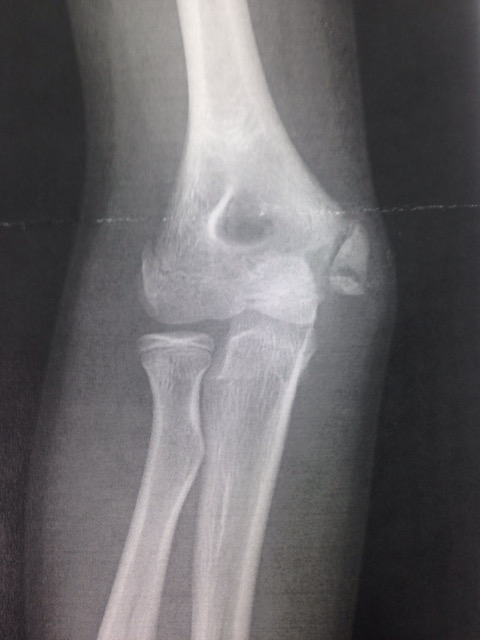

野球肘は内側型・外側型・後方型に分類されます。

○内側型:上腕骨内上顆下端裂離・分節、上腕骨内上顆骨端離開・分節、鈎状結節部裂離、内側側副靭帯損傷、内側上顆炎など

○外側型:上腕骨小頭部離断性骨軟骨炎、滑膜ヒダ障害、外側上顆炎など

○後方型:肘頭骨端離開など